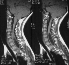

A condition which is defined by a tubular cavity which contains fluid within the spinal cord.

Rapidly progressive scoliosis, Upper thoracic curve, Left thoracic curve, High double thoracic curve, Cervical bony , nomalies, Erosion of cervical bodies, Widened spinal canal, Basilar invagination, Cervical ribs

Diagnosis:

Suspect if C5 canal is 6mm greater than body. If it is 4mm there is a 3:1 probability of syrinx.

If C5 canal is wider than C6 body - suspect.